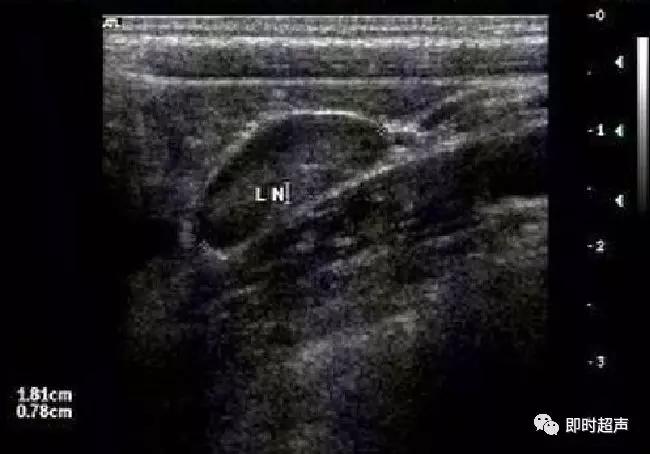

肠系膜淋巴结肿大超声表现

超声诊断小儿肠系膜淋巴结炎

正常肠系膜淋巴结直径小于7mm;同一区域肠系膜上有2个以上淋巴结显像,淋巴结长轴直径大于10mm,短轴直径大于5mm,纵横比大于等于2为肿大;横径大于1.5CM提示病理性肿大。淋巴结内血流的分布:血流信号沿淋巴门分布,该型通常见于非特异性炎的淋巴结。RI在0.59~0.68之间。